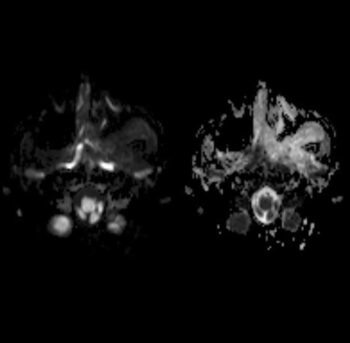

Tumor benigno (no canceroso) formado por vasos sanguíneos y tejido fibroso. Los angiofibromas nasofaríngeos juveniles aparecen en la parte posterior de la nariz y a veces se diseminan a la parte superior de la garganta, los senos paranasales y los huesos que rodean los ojos; en muy pocas ocasiones se diseminan al cerebro. Los signos y síntomas son secreción nasal, hemorragia nasal, dificultad para respirar por la nariz, sordera y tendencia a formar moretones. Los angiofibromas nasofaríngeos juveniles son más frecuentes en hombres jóvenes. Son un tipo de tumor vascular.

Imágenes de resonancia magnética.